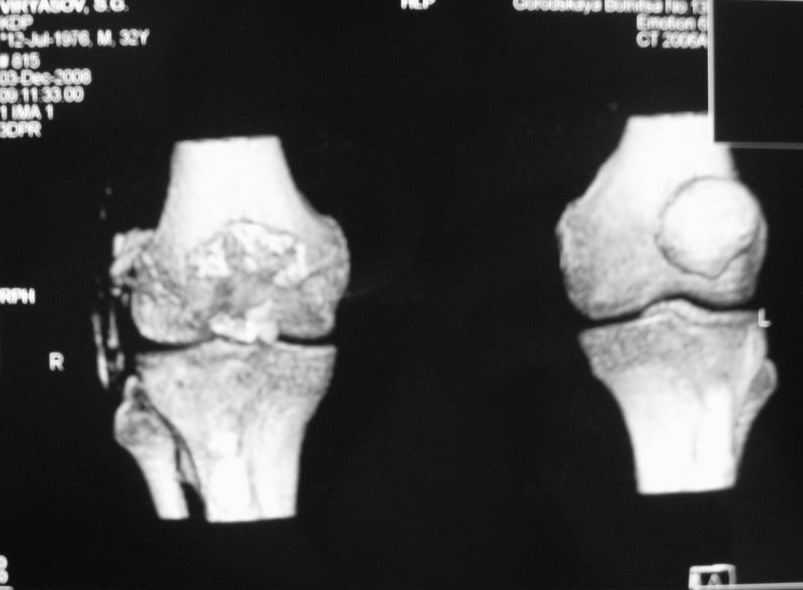

Уважаемые коллеги! Обратился пациент 32 лет с травмой коленного сустава от июля 2008 года - падение с мотоцикла, прямой удар передней поверхностью коленного сустава. Диагноз - открытый оскольчатый перелом надколенника. В одной из больниц города выполнили ПХО, шов надколенника лавсаном. Заживление раны с частичным нагноением(разведена на участке 3 см).Сейчас мягкие ткани в порядке. R-снимки, КТ в приложении. Объем движений 0/0/110 гр.Ходит почти без хромоты. Жалобы на торчащий под кожей один из отломков, боль в этой точке. Вопрос: что делать? Первое - убрать этот отломок и на этом закончить. Второе - оставить все как есть(отломок не так уж и сильно мешает). Ждать возможного развития артроза, дальше по ситуации. Третье - подумать о протезировании надколенника.

Внешний вид коленного сустава

Судя по фото, объём движений достаточный, деформация стрктур колена, визуально, тоже не очень выражена. Развитие артроза в сегодняшнем состоянии и после протезирования прогнозировать дело неблагодарное. Так что может действительно решить те вопросы и неудобства, которые на сегодняшний день беспокоят пациента, а далее осуществить динамическое наблюдение (протезирование надколенника никуда в принципе не уйдет). Просто в жизни бывают ситуации когда поговорка "лучшее враг хорошего", актуальна. С уважением Михаил.